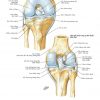

Atlas Giải Phẫu Chi Dưới (Netter) | Bài giảng CĐHA

* Tác giả: Frank H. Netter v6 – 2016